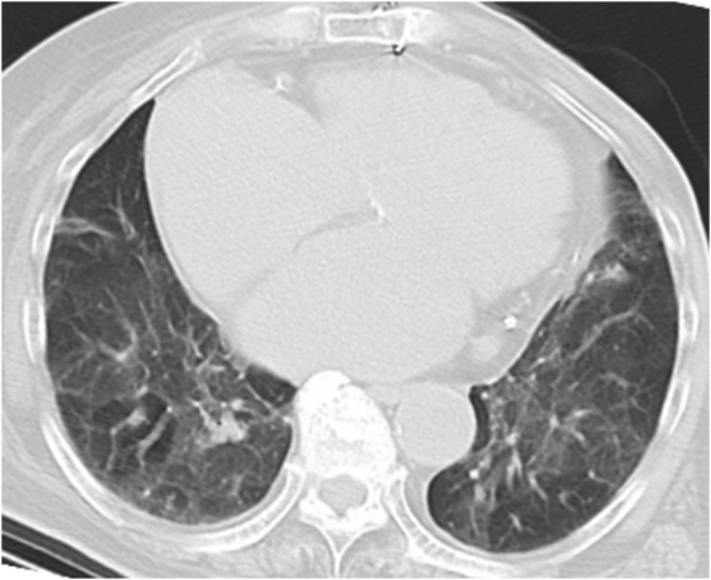

After transfer to our hospital, the patient was reassessed carefully. There were no complaints of cough, dyspnea, or taste disorder. However, mild dementia was noted. Before the injury, she was able to walk with a cane. On physical examination, a shortened externally rotated left lower extremity with no peripheral neurovascular deficit was evident. Her vital signs on admission were as follows: blood pressure, 136/88 mmHg; heart rate, 84 beats/min; body temperature, 37.1 °C; respiratory rate, 18 breaths/min; and oxygen saturation with room air, 90%. A chest radiograph did not demonstrate any lung abnormalities except for a cable at the site of the previous cardiac surgery and marked cardiac enlargement. Computed tomography (CT) revealed diffuse trivial pulmonary edema in both lungs (Fig. 1 ). There were no ground grass opacities, crazy-paving patterns, or any other findings that assumed COVID-19 [10]. Radiographs of the left hip revealed a pertrochanteric fracture with features consistent with three-part fragments (AO 31A2.2, Fig. 2 ). Three-dimensional CT showed a large oblique fragment consisting of the greater trochanter and the lesser trochanter (Shoda classification [11]; three-part G-L) (Fig. 3 ). PCR analysis for COVID-19 was again performed on admission, and the test result was positive.

Fig. 1.

Chest computed tomography at the time of admission to the previous hospital shows diffuse trivial pulmonary edema in both lungs.